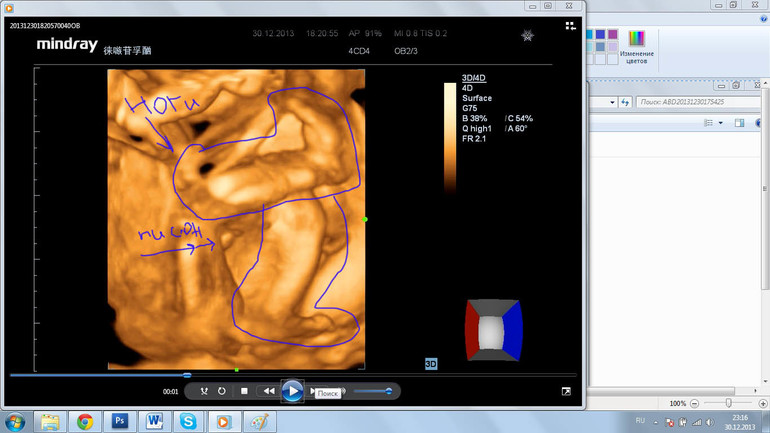

Нашла еще видео, нам оказывается записали, там есть вид сбоку...Писюн же, ну? :)))